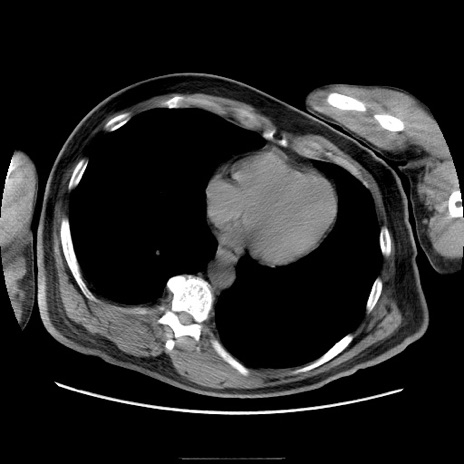

症例22(横断像)

【症例】50歳代男性

【主訴】腹痛

【現病歴】AVMからの被殻出血のため回復期リハ病棟入院中。 本日午後3時頃急に下腹部痛が出現した。

【既往歴】AVM、被殻出血、虫垂炎、高血圧

【身体所見】意識晴明、左半身不全麻痺、会話の理解は良好、36.5°C、腹部:膨隆、全体に板状硬、下腹部正中に圧痛点あり、反跳痛-、筋性防御不明、右下腹部にope scar

【データ】WBC 9400、CRP 0.06